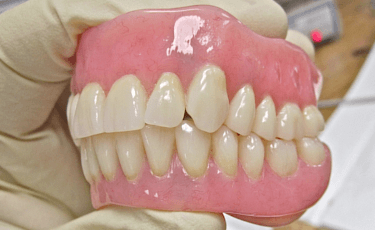

入れ歯 ![]() |

歯を失った部分の型取りをし、